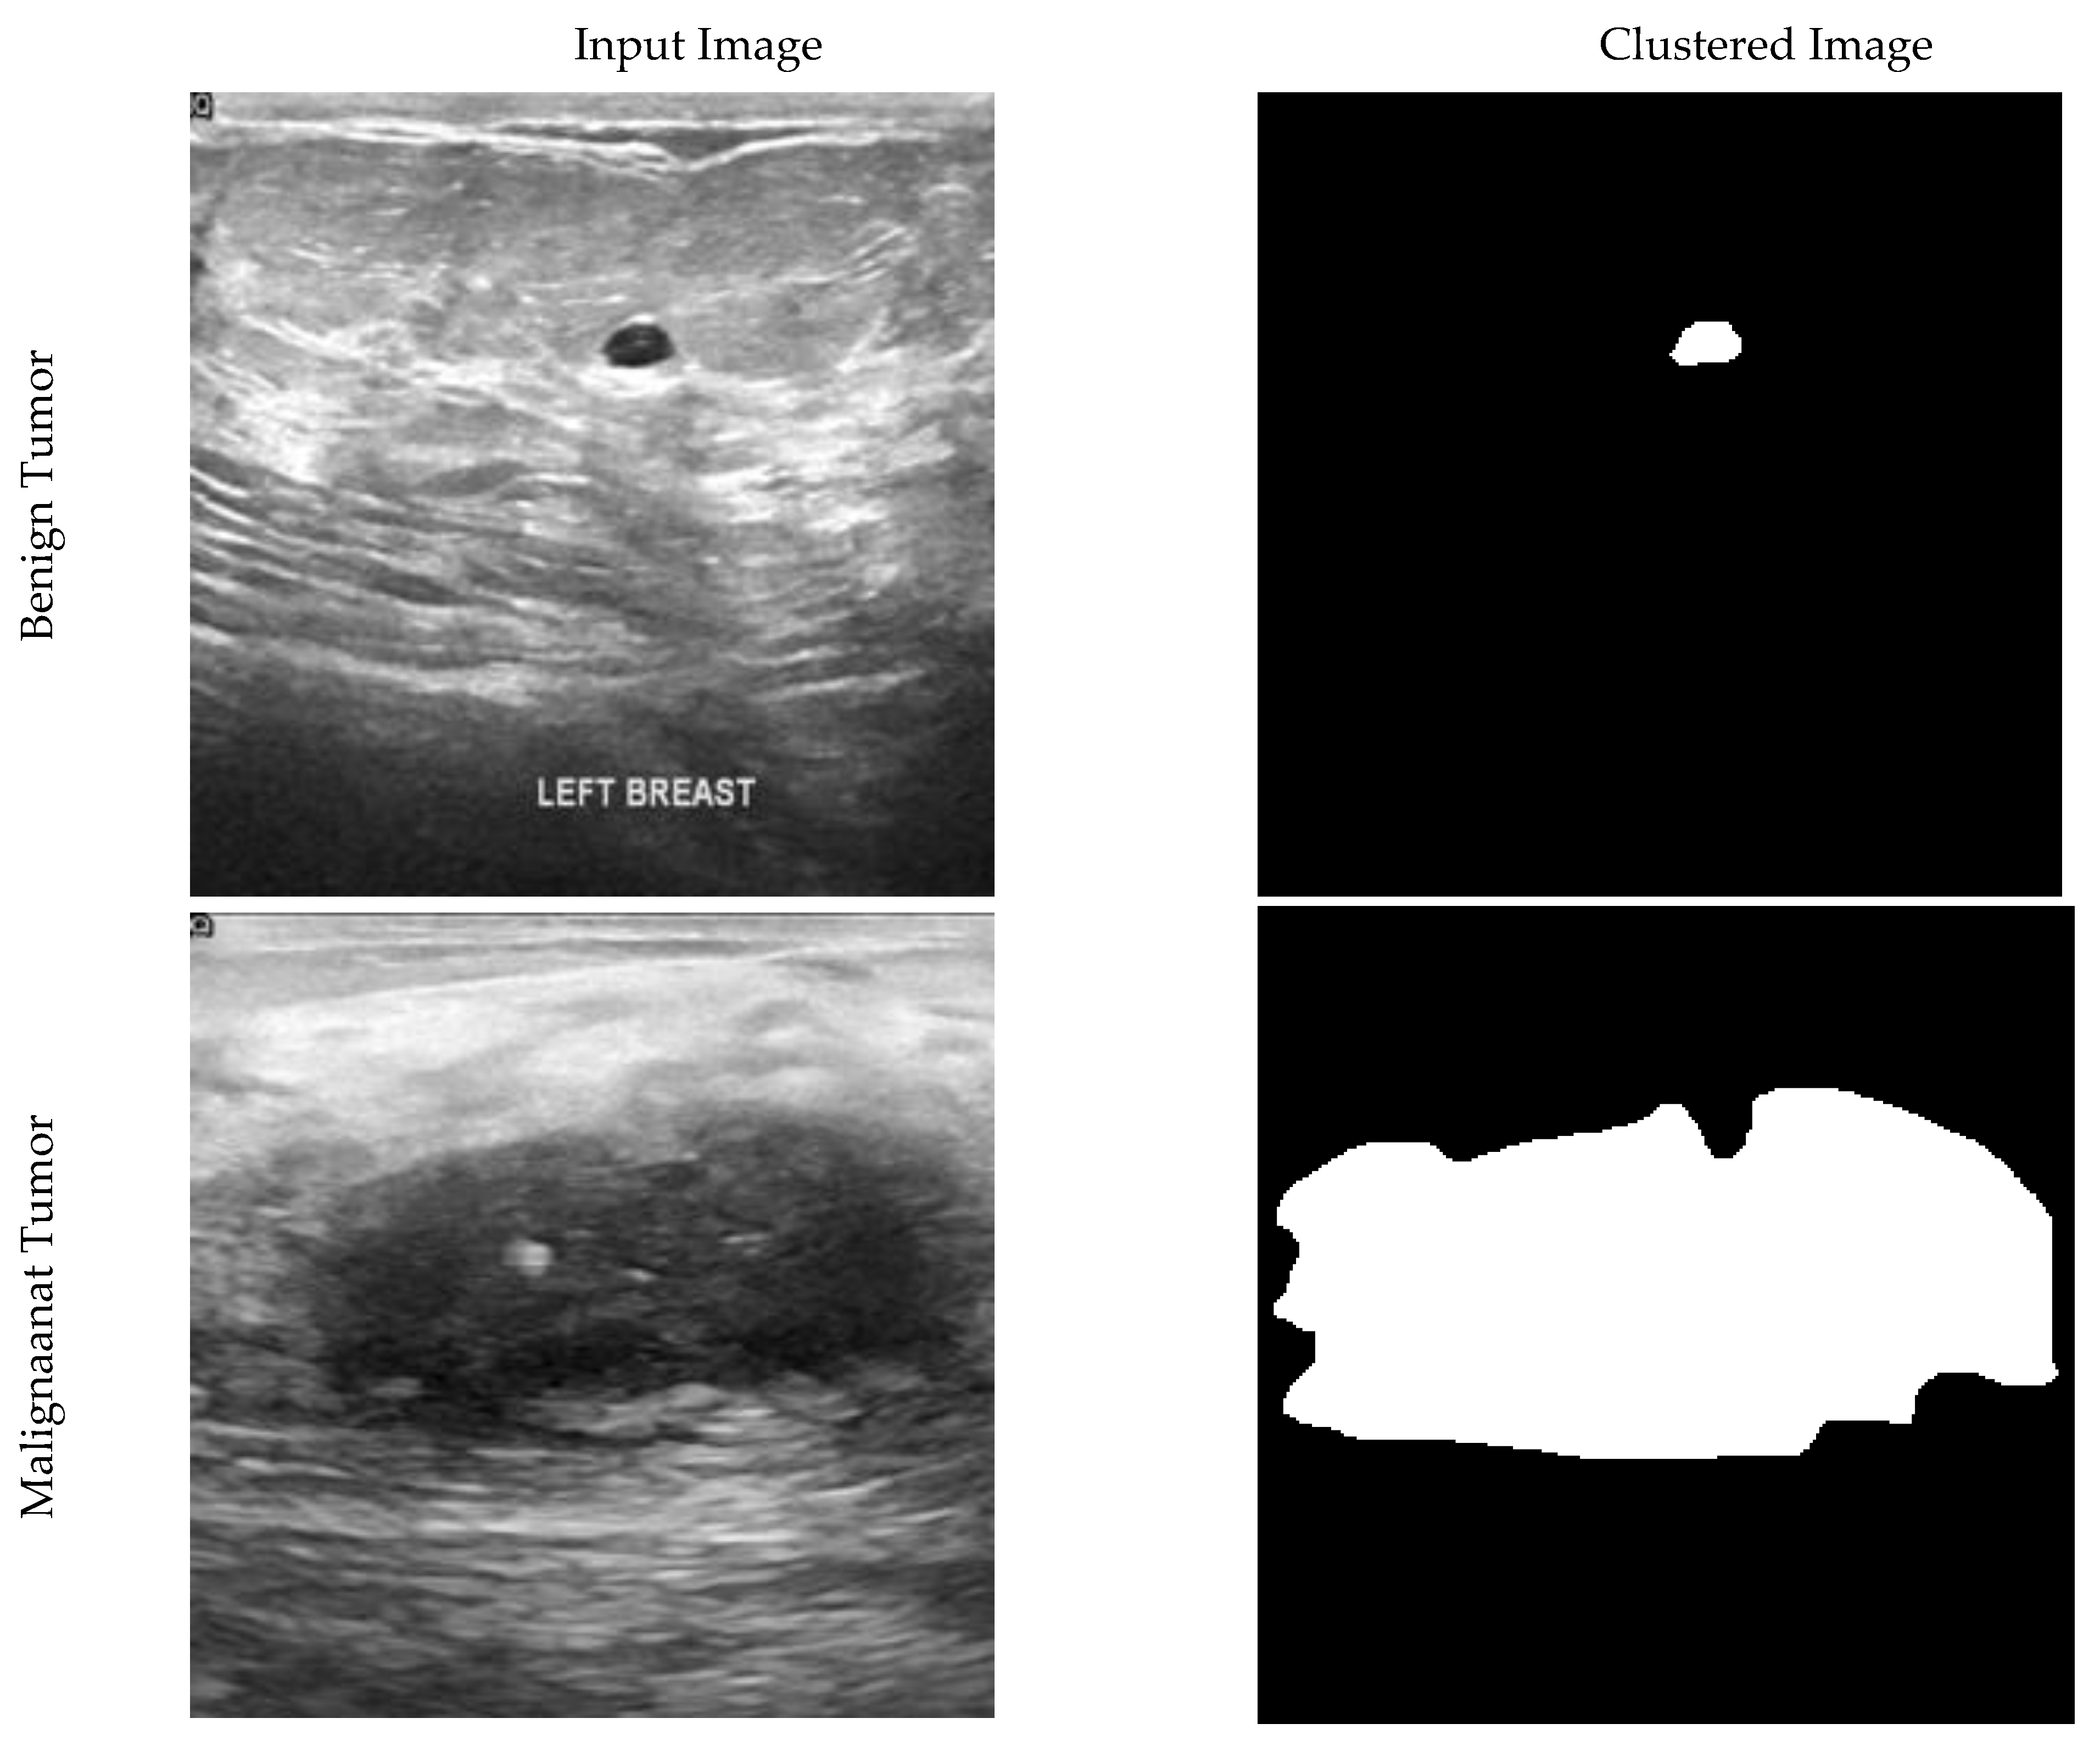

In this paper, segmentation of images has been used to find the primary location of the tumor. Segmentation is not one of the main steps of the convolution and DL algorithm. It has been used to validate the results. By separating pixels with zero values as the background, each non-zero pixel is the mass breast threshold (225). Each remaining pixel is 127 to the normal breast tissue, as shown in Figure 1.

Figure 1.

Ultrasound and clustered images of breast cancer for benign, malignant, and normal tissue conditions.